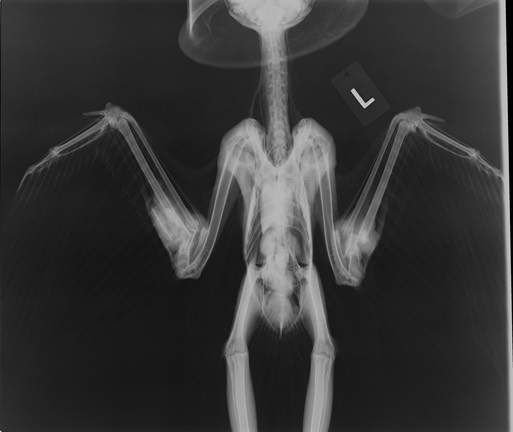

Barn Owl 18-648

We are not sure what this Barn Owl collided with, but her left scapula is fractured and her right shoulder is compromised. We immobilized the scapula by bandaging the left wing to the body. She kept getting tangled up in her right wing, but we had a challenging time finding a bandage technique that would keep her wing in a normal position without causing more problems than it solved. We finally settled on a figure-eight bandage that kept the right wing from extending, but didn’t keep it fastened to the body. She is able to stay upright and eat her mice.

Try sitting down on the ground with both arms firmly fastened to your body, then try standing up again to get an idea of what it would be like for the owl to have both wings completely immobilized.